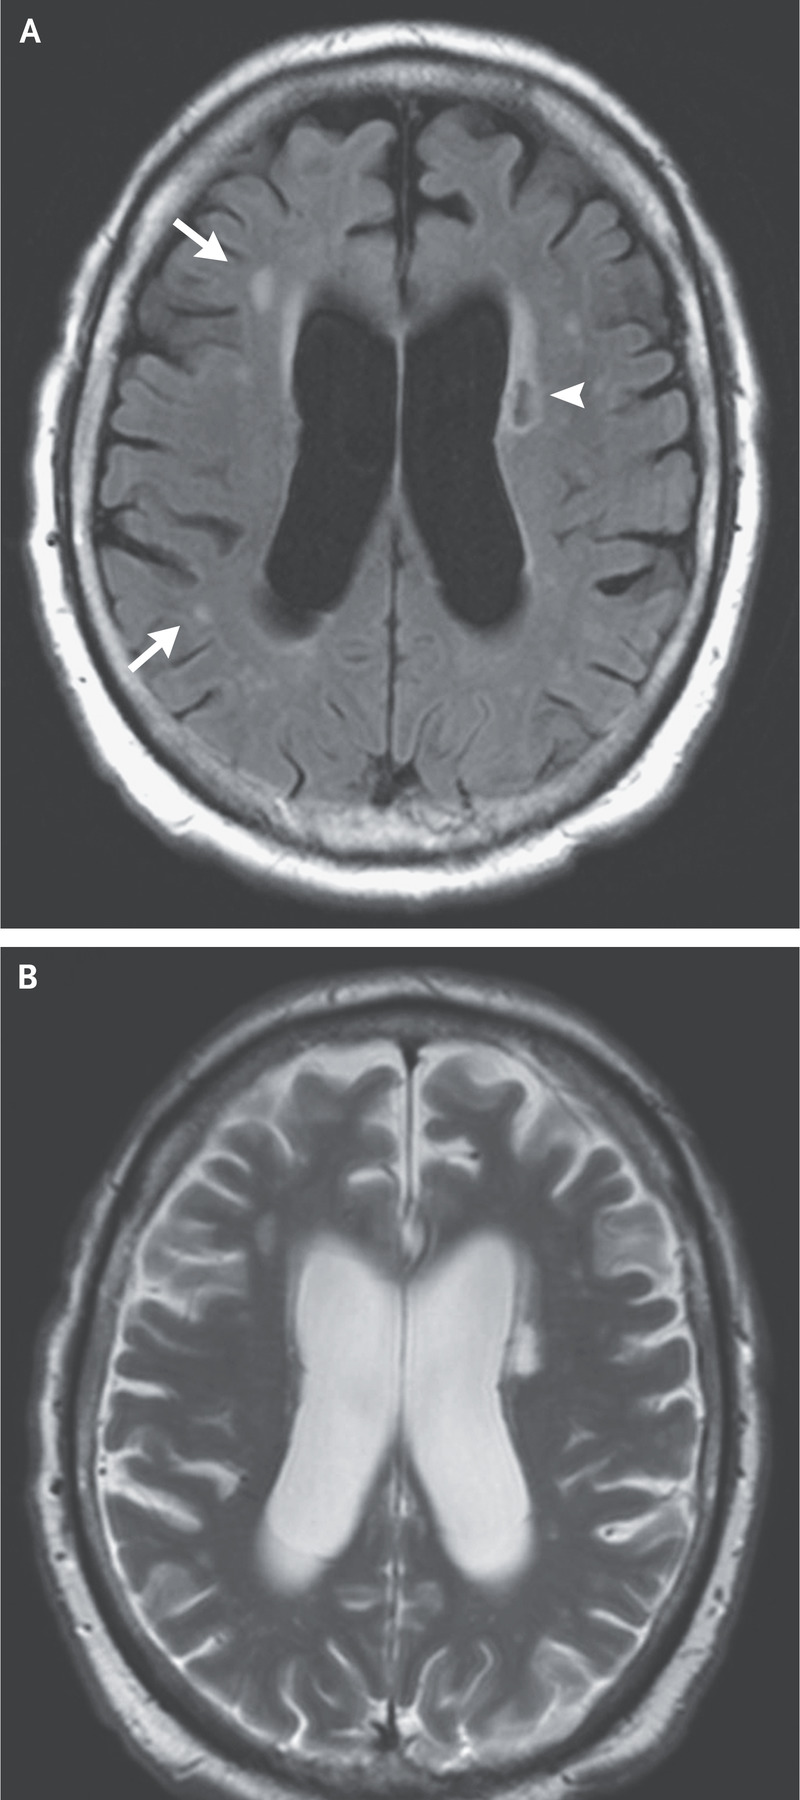

You perform a lumbar puncture and the opening pressure and analysis of the cerebral

spinal fluid are both normal. The results of an axial fluid-attenuated inversion recovery

MRI image (Panel A) and a T2-weighted MRI image (Panel B) are shown below.

The arrow head points to an old lacunar infarct in the corona radiata; the arrows point to scattered hyperintensities suggestive of small-vessel ischemic changes.